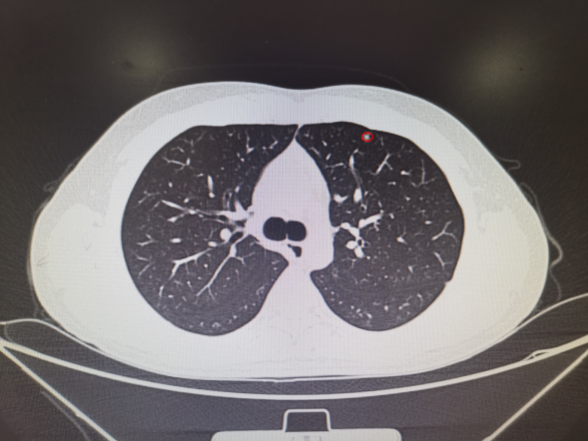

其中消融患者的肺结节位于左肺下叶外基底段24级支气管,膈肌腱部后缘,大小8mm,受呼吸运动影响大,技术难度极大,堪称肺消融治疗的“珠穆朗玛峰”。柳教授团队顺利完成了该例患者治疗,填补了福建省多项肺小结节诊断及治疗技术的空白,同时意味着,那些心肺功能无法耐受开放或者胸腔镜肺小结节手术的患者以及双肺多枚肺小结节需要同时手术的患者有机会获得更多精准且彻底治疗的可能性。